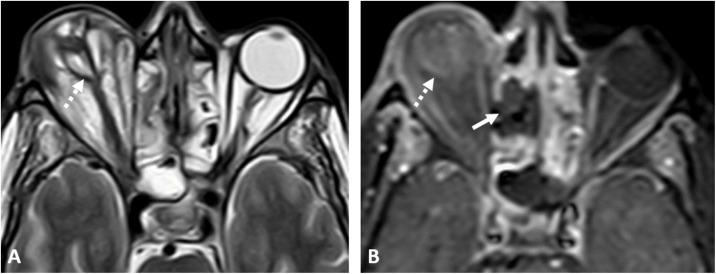

This is a case series presenting the radiologic features and clinical presentation of acute invasive fungal rhino-orbital-cerebral sinusitis (AIFS) in eight hospitalized patients with confirmed COVID-19 infection.

Our patient cohort presented with symptoms of the invasive fungal disease within 12-35 days from their initial presentation with COVID-19 infection. The cross-sectional imaging features of AIFS associated with COVID-19 infection do not differ from those reported in the literature for AIFS associated with other risk factors, yet our patients had features of aggressive late-stage forms with high morbidity and mortality rate.